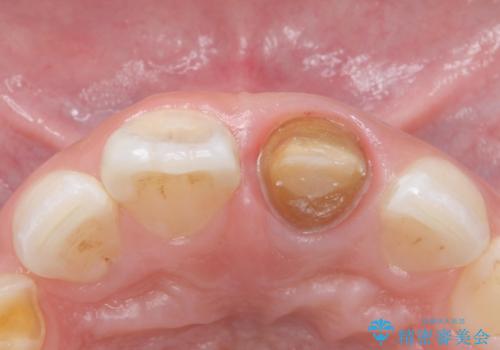

- 前歯の変色を主訴に来院された患者様です。

根管治療からのやり直しをした後、ジルコニアクラウンで色調の改善をしていきます。